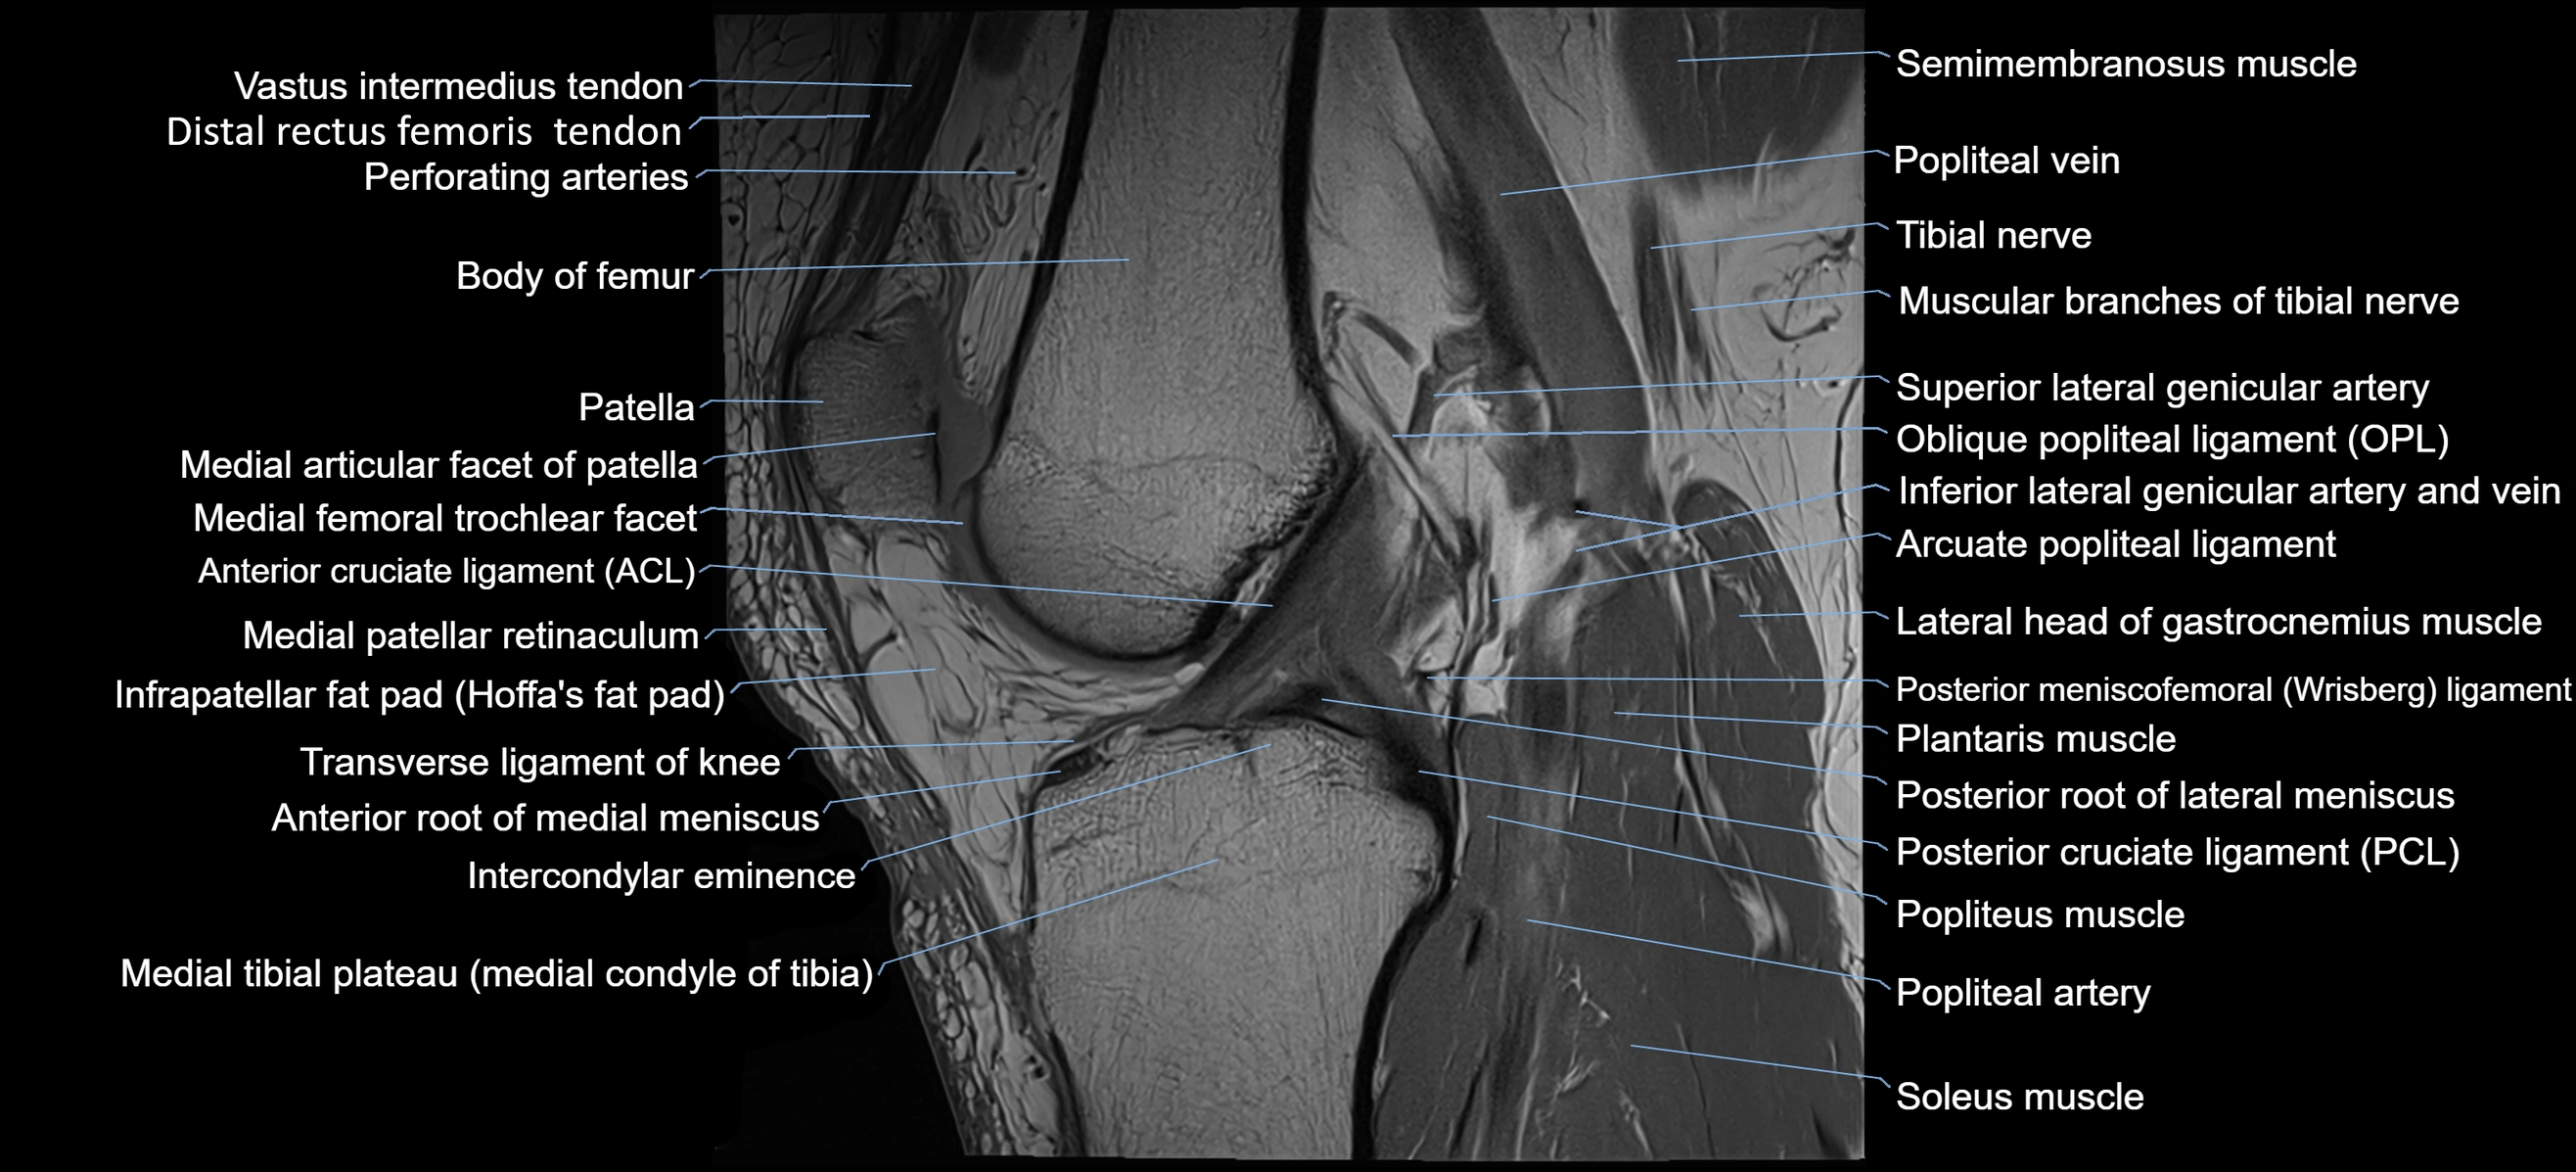

- Anterior cruciate ligament

- Anterior root of medial meniscus

- Arcuate popliteal ligament

- Body of femur

- Distal rectus femoris tendon

- Distal vastus intermedius tendon

- Intercondylar eminence

- Lateral head of gastrocnemius muscle

- Medial articular facet of patella

- Medial patellar retinaculum

- Medial tibial plateau

- Muscular branches of tibial nerve

- Oblique popliteal ligament

- Patellar tendon (patellar ligament)

- Plantaris muscle

- Popliteal artery

- Popliteal vein

- Popliteus muscle

- Posterior cruciate ligament

- Posterior meniscofemoral ligament

- Posterior root of lateral meniscus

- Posterior root of medial meniscus

- Semimembranosus muscle

- Soleus muscle

- Superior lateral genicular artery

- Transverse ligament of knee